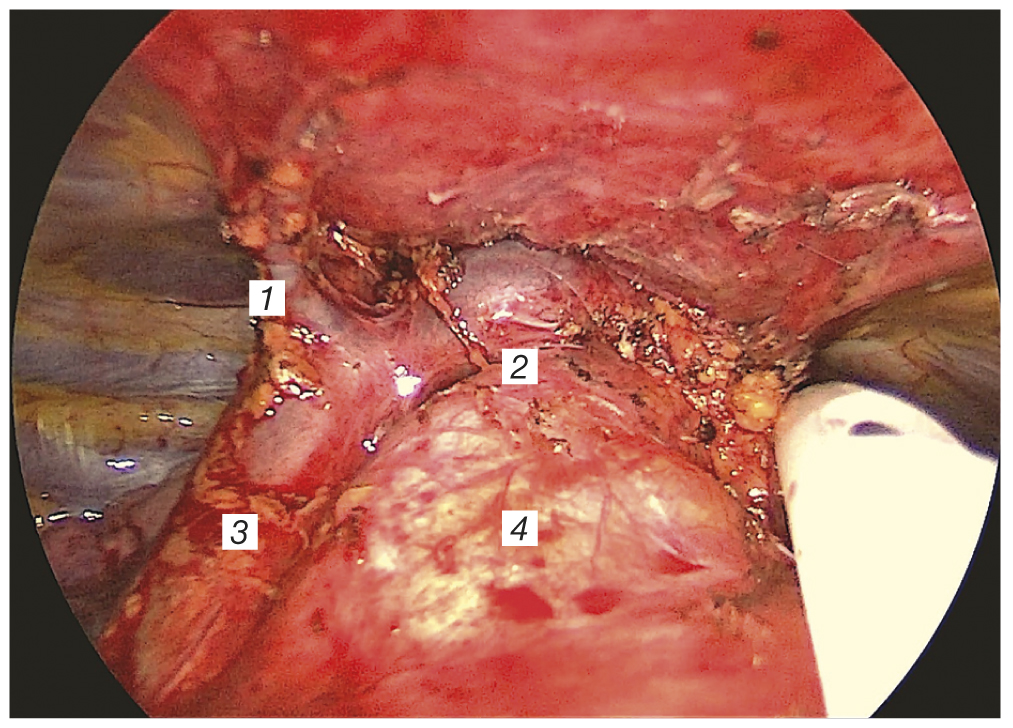

The dissection of tissues was performed along both phrenic nerves (Fig. 4), after which followed the isolation of the brachiocephalic vein with the processing of the thymic vein (Fig. 5). The vessels with a diameter more than 5 mm were preferably processed using the clips. The important step of surgery was the isolation of the cervical portion of thymus. The objective of the surgical intervention was to remove the whole thymic tissue, including the tumor.

Fig. 4. Thoracoscopic thymectomy from a uniportal subxiphoid approach. Stage of pericardial separation. 1 — thymic tissue; 2 — pericardium; 3 — right lung; 4 — superior vena cava.